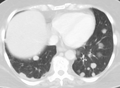

سرطان منتشر في الرئتين

- الرئتين: السعال، ونفث الدم وضيق التنفس[9]